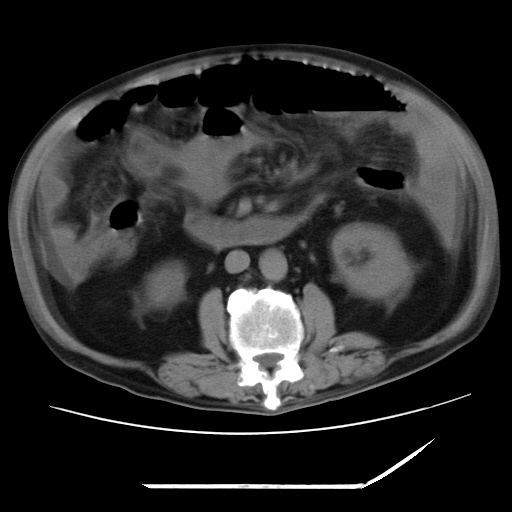

以下是引用zxl51642在2009-8-12 18:55:00的发言:[br]1、肠系膜脂肪浑浊,密度增高,腹水,支持腹膜炎诊断;2、右肾盂及输尿管中段结石,左输尿管起始段结石;3、胆囊切除术后改变?4、双侧胸膜腔少量积液;5、胰腺体积不大,勾勒清楚,肾前筋膜无增厚,不支持胰腺炎,请结合血尿淀粉酶及临床。